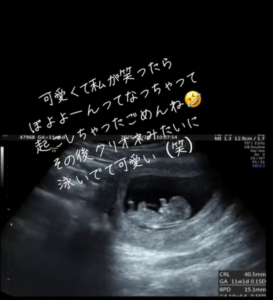

人の形をしっかり確認(@kokogun5656さんより提供)

ところが、ママさんが笑った瞬間の振動が、お腹の中の赤ちゃんにまで届いたようです。直後、眠っていた赤ちゃんが動き出したのでした。

ママさんが『ぽよよーん』と表現したその一連の動きは、多くの人の注目を集めることに。投稿には「母性が溢れ出す…!」「クリオネちゃん」「可愛すぎる」などの声が寄せられていました。

赤ちゃんが浮いた瞬間(@kokogun5656さんより提供)